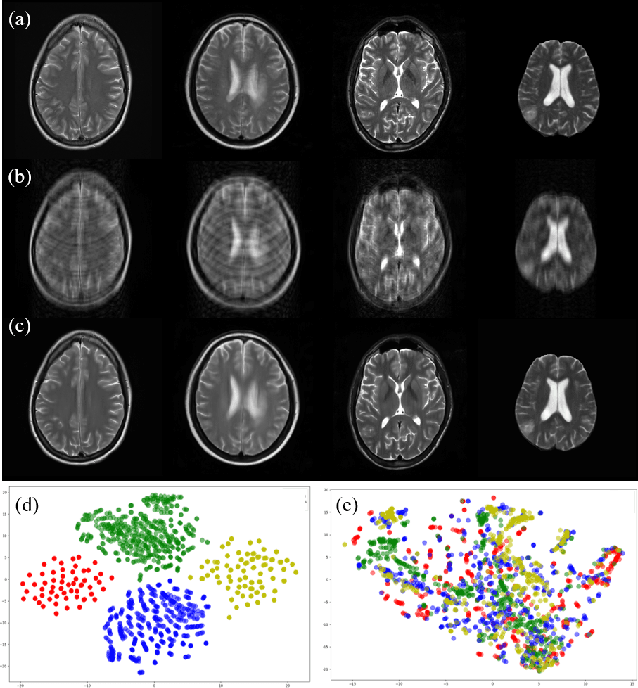

Abstract:The synergy of long-range dependencies from transformers and local representations of image content from convolutional neural networks (CNNs) has led to advanced architectures and increased performance for various medical image analysis tasks due to their complementary benefits. However, compared with CNNs, transformers require considerably more training data, due to a larger number of parameters and an absence of inductive bias. The need for increasingly large datasets continues to be problematic, particularly in the context of medical imaging, where both annotation efforts and data protection result in limited data availability. In this work, inspired by the human decision-making process of correlating new ``evidence'' with previously memorized ``experience'', we propose a Memorizing Vision Transformer (MoViT) to alleviate the need for large-scale datasets to successfully train and deploy transformer-based architectures. MoViT leverages an external memory structure to cache history attention snapshots during the training stage. To prevent overfitting, we incorporate an innovative memory update scheme, attention temporal moving average, to update the stored external memories with the historical moving average. For inference speedup, we design a prototypical attention learning method to distill the external memory into smaller representative subsets. We evaluate our method on a public histology image dataset and an in-house MRI dataset, demonstrating that MoViT applied to varied medical image analysis tasks, can outperform vanilla transformer models across varied data regimes, especially in cases where only a small amount of annotated data is available. More importantly, MoViT can reach a competitive performance of ViT with only 3.0% of the training data.

Abstract:Data-driven automatic approaches have demonstrated their great potential in resolving various clinical diagnostic dilemmas for patients with malignant gliomas in neuro-oncology with the help of conventional and advanced molecular MR images. However, the lack of sufficient annotated MRI data has vastly impeded the development of such automatic methods. Conventional data augmentation approaches, including flipping, scaling, rotation, and distortion are not capable of generating data with diverse image content. In this paper, we propose a generative adversarial network (GAN), which can simultaneously synthesize data from arbitrary manipulated lesion information on multiple anatomic and molecular MRI sequences, including T1-weighted (T1w), gadolinium enhanced T1w (Gd-T1w), T2-weighted (T2w), fluid-attenuated inversion recovery (FLAIR), and amide proton transfer-weighted (APTw). The proposed framework consists of a stretch-out up-sampling module, a brain atlas encoder, a segmentation consistency module, and multi-scale labelwise discriminators. Extensive experiments on real clinical data demonstrate that the proposed model can perform significantly better than the state-of-the-art synthesis methods.